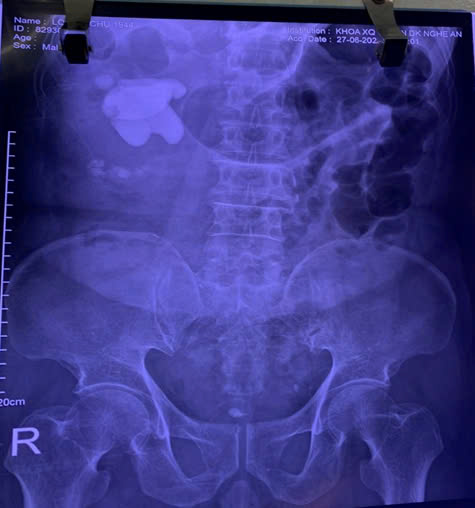

Hình Ảnh mổ mở lấy sỏi san hô bên phải tại Bệnh

viện HN Đa khoa Nghệ An